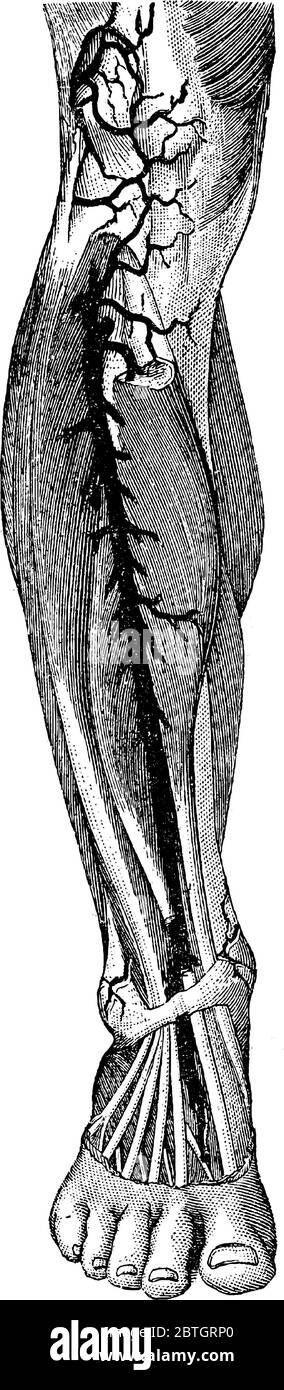

RF2BTGRP0–Artère située devant la jambe droite humaine. Une artère est un vaisseau qui transporte le sang loin du coeur et vers d'autres tissus et organes , vin